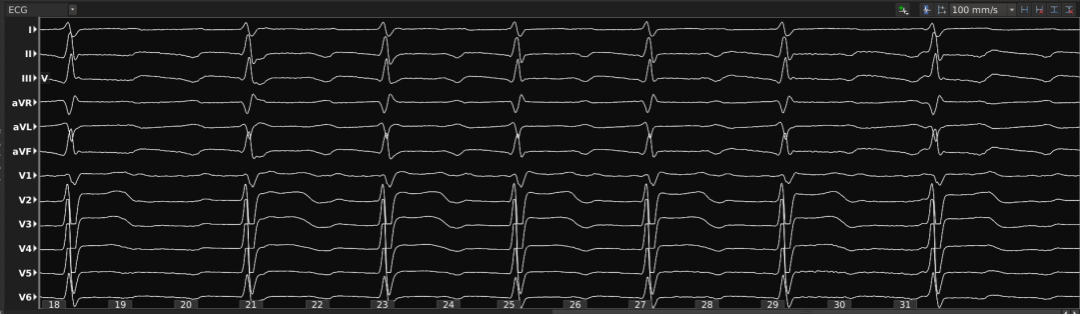

AFL ECG EGM

男,59岁,20年前行心脏瓣膜(主动脉瓣人工机械瓣)置换术,近期因胸闷心悸3天入院。